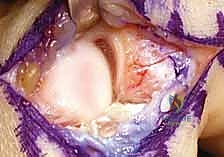

عندما يكون عدم الاستقرار مزمناً، أو عندما تضمر أنسجة الرباط الأصلي بحيث لا يمكن خياطتها مباشرة، يقرر الأستاذ الدكتور محمد هطيف إجراء عملية "إعادة بناء الأربطة" (Ligament Reconstruction). تُعد هذه الجراحة من أدق جراحات العظام وتتطلب مهارة ميكروسكوبية عالية لضمان التثبيت التشريحي الدقيق.

فيما يلي استعراض تفصيلي وحصري للخطوات الجراحية كما تُجرى في غرف العمليات المجهزة بأحدث التقنيات تحت إشراف الدكتور هطيف: